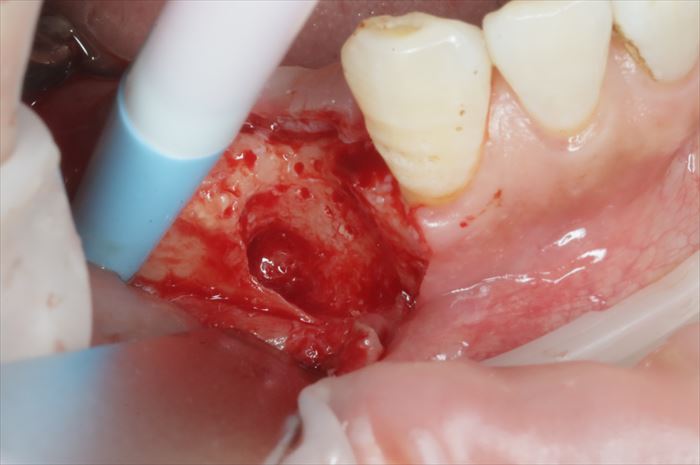

インプラント撤去直後の状態です。

粘膜を剥離して炎症性の肉芽組織を取り除きます。

不良肉芽を骨表面から剥がすことができました。

骨表面から剥離した不良肉芽組織を切除し、皮質骨穿孔(デコルチケーション)を終えました。

デコルチケーションとは骨内部からの出血を促し、骨性の治癒を期待するためです。